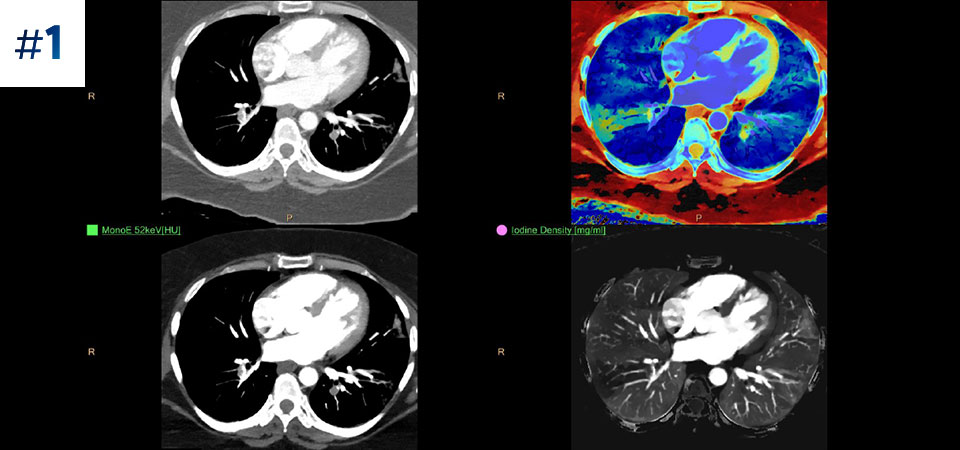

Vá além da CT convencional. Veja de que forma os vários tipos de resultados obtidos com deteção espectral podem aumentar a fiabilidade do seu diagnóstico.

A nossa CT com detetor espectral da Philips permite obter dados convencionais e espectrais numa única aquisição, sem qualquer alteração do nosso atual fluxo de trabalho.